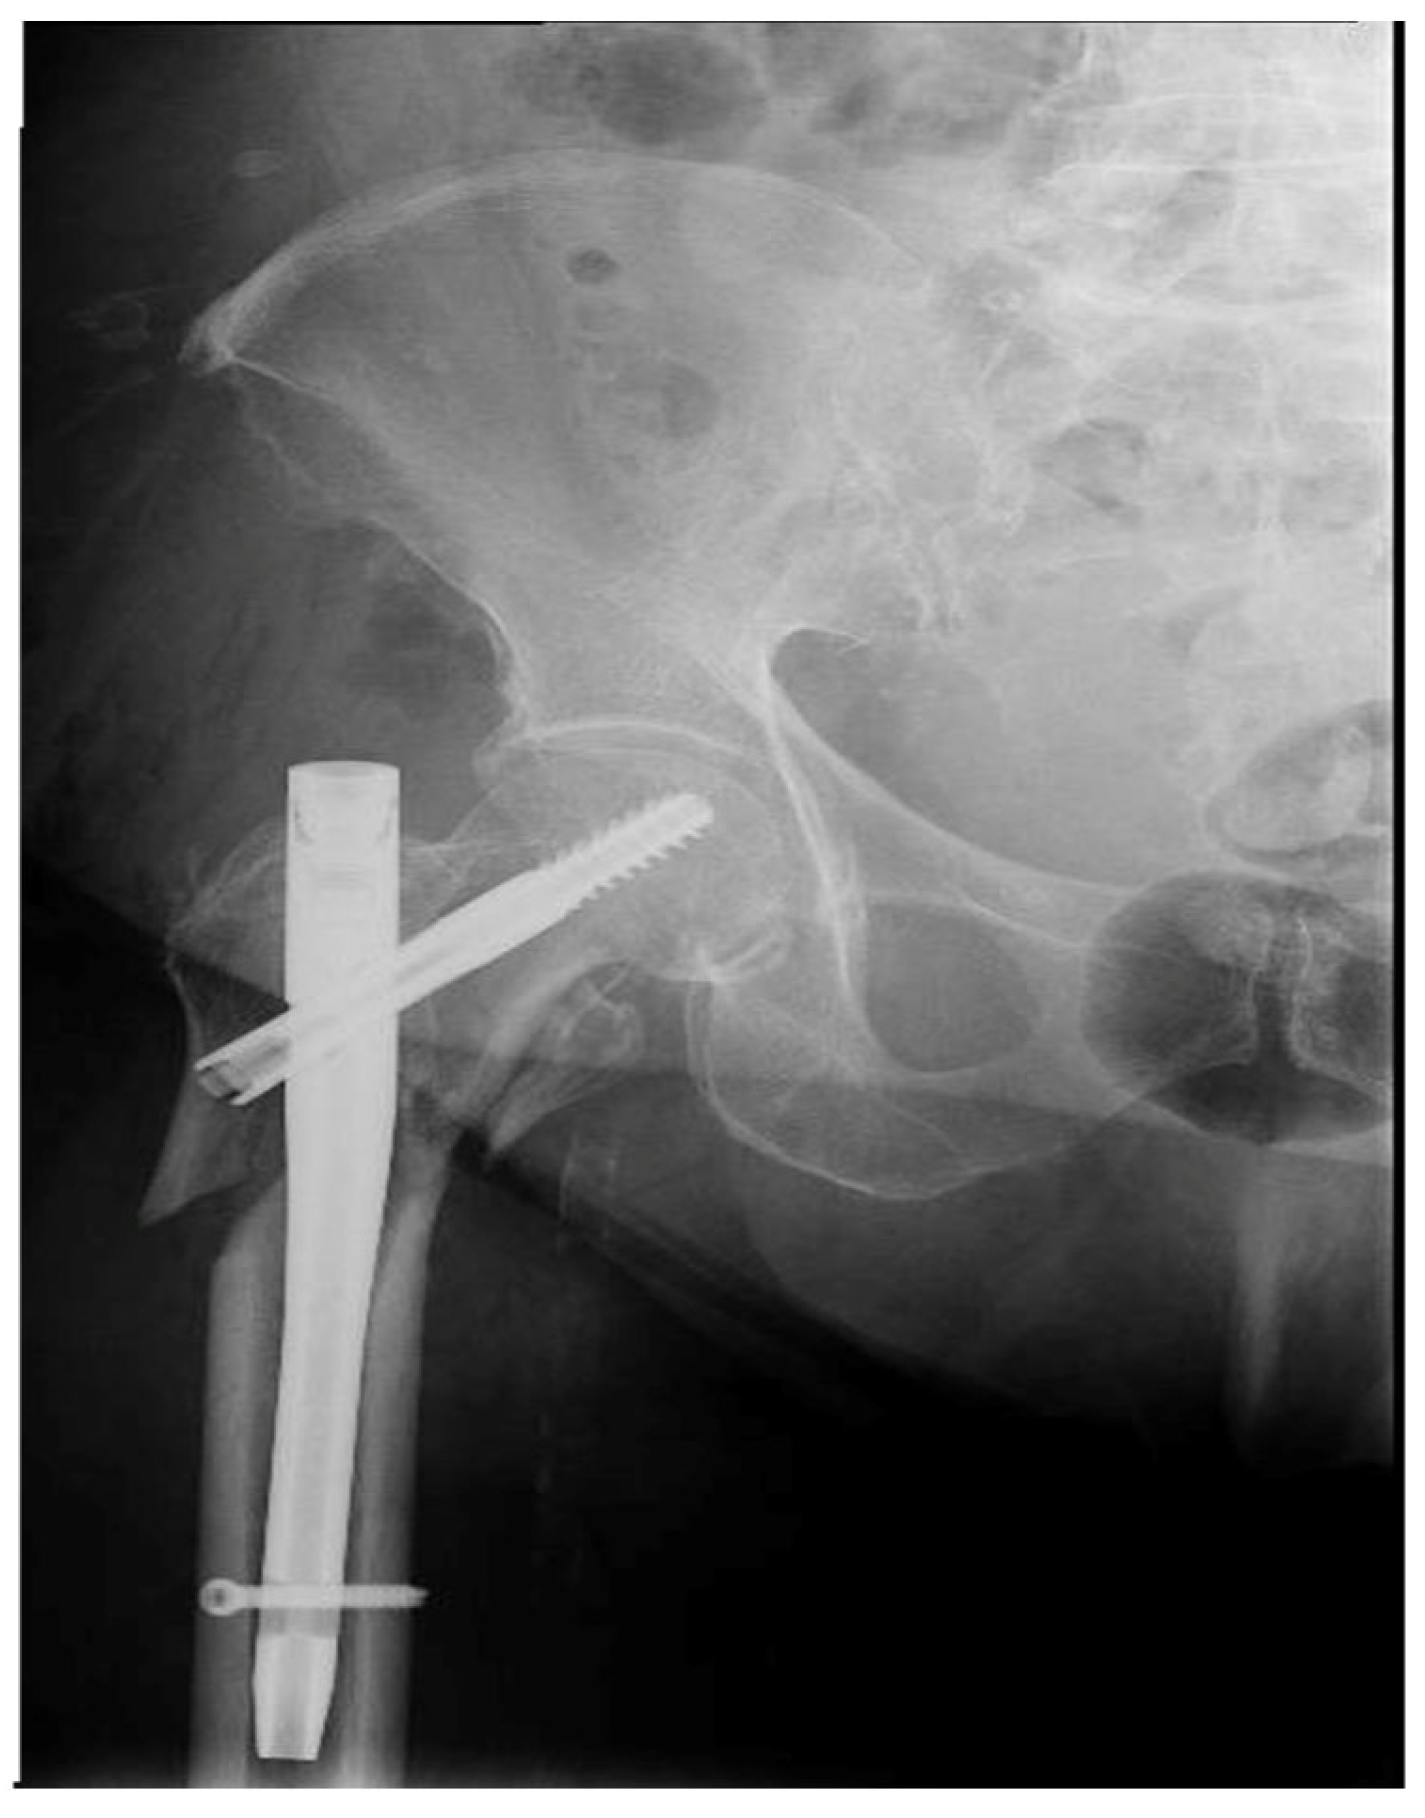

4.1. Clinical Case History of the Failed Gamma Nail

| Radiologic images study | Visualization of the bone and implant. |